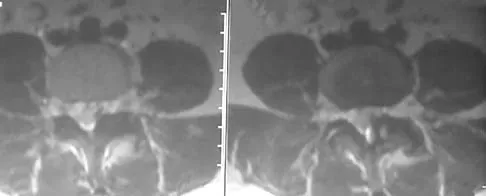

A 30-year-old man has had intermittent swelling of his right ankle for the past 6 months. He denies any history of trauma. Radiographs reveal osteolytic changes on both sides of the joint. An axial CT scan and a T2-weighted MRI scan are shown in Figures 40a and 40b. He undergoes surgical excision. An intraoperative photograph and a biopsy specimen are shown in Figures 40c and 40d. What is the most likely diagnosis?

Explanation